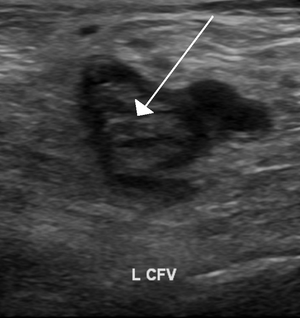

An ultrasound image demonstrating a blood clot in the left common femoral vein.